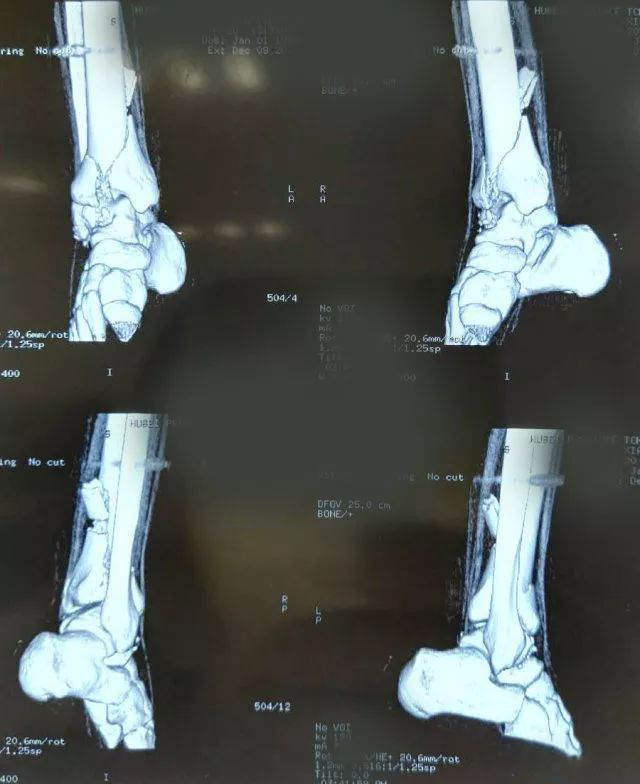

一起来看一个病例:男,20岁,摔倒右踝3天,体格检查示右小腿下段肿胀压痛,活动受限,运动感觉可,诊断为右侧 Pilon骨折。X片及CT三维图如下,欢迎投票并在评论区附上理由。